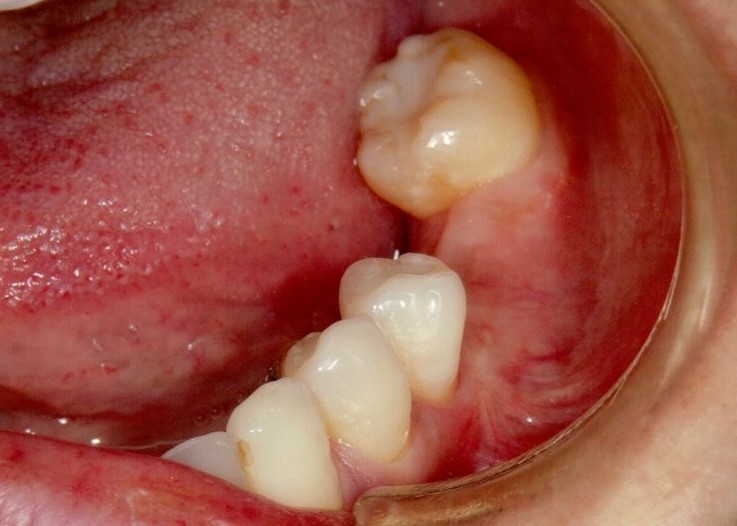

奥歯インプラント(スクリュー固定)

(伊東市 女性)

治療の流れ

むし歯で歯を失ってしまいました。

インプラントを埋入し、最終的な被せ物を装着しました。(ネジ穴をふさぐ前)

ネジ穴をふさぐとこの様な状態になります。

インプラント手術:250,000円

静脈内鎮静法:0円

既製アバットメント:90,000円

メタルボンド:130,000円

総額:470,000円+税